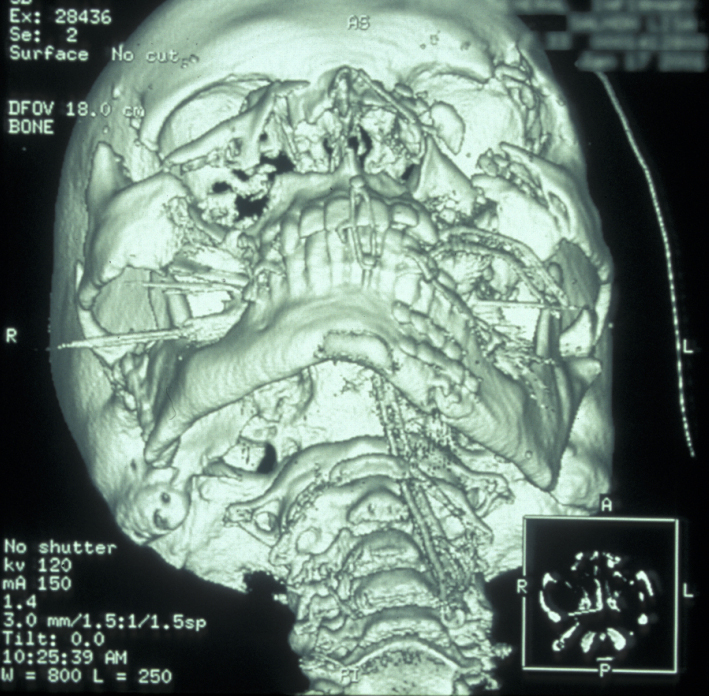

If the patient is unable to stand in the DPT machine, left and right lateral oblique mandibular views will give good imaging of the body of the mandible.  If the patient has multiple complex maxillofacial fractures a CT scan (CT coronal and axial images, with or without 3D reformatting) is helpful (see Figure 4). The CT scan will help assess condylar fracture position, angulation and any fractured dislocation of the condylar head. A CT scan is also useful to image multi-part mandibular body fractures.

Figure 4: CT scan of a displaced mandibular fracture.

Figure 5: CT scan of bilateral condylar fractures; note the overlap of fragments.

Plain film X-ray radiographs from different angles (occipitomental views) give some information, but a much more accurate assessment of the extent of the fracture can be obtained from CT scans (see Figure 11 for an example).

CT scans also allow 3D reformatted images of the facial skeleton to be produced as shown in Figure 12.

Figure 12: Three-dimensional reconstruction of a midface fracture.